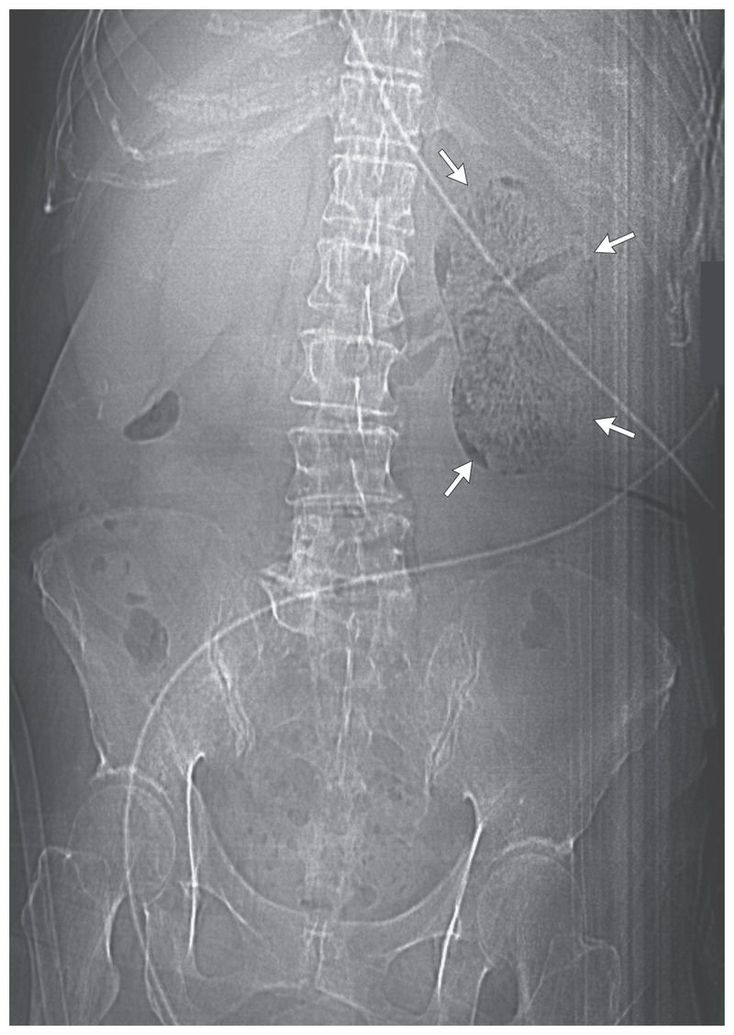

A 67-year-old woman with diabetes and poor glycemic control who had recently been treated for pyelonephritis presented to the emergency department in septic shock. She had a 2-day history of fever, flank pain, lethargy, and confusion. Blood tests showed leukocytosis and hyperglycemia. Urinary microscopy revealed pyuria. A scout image was obtained with the use of unenhanced computed tomography. The image revealed extensive gas collection in the parenchyma and perinephric space of the left kidney (arrows) and the left renal vein, with corresponding hydronephrosis and hydroureter. These findings and her symptoms suggested emphysematous pyelonephritis. Immediate radical nephrectomy was performed. Escherichia coli was found on blood cultures, and a course of piperacillin–tazobactam was administered. Despite intraoperative perforation of the bladder, which required surgical repair, the patient had a good postoperative recovery and remained well after the completion of antibiotic treatment, with good glycemic control. Elevated tissue levels of glucose in patients with diabetes may create a more favorable environment for gas-forming bacteria.